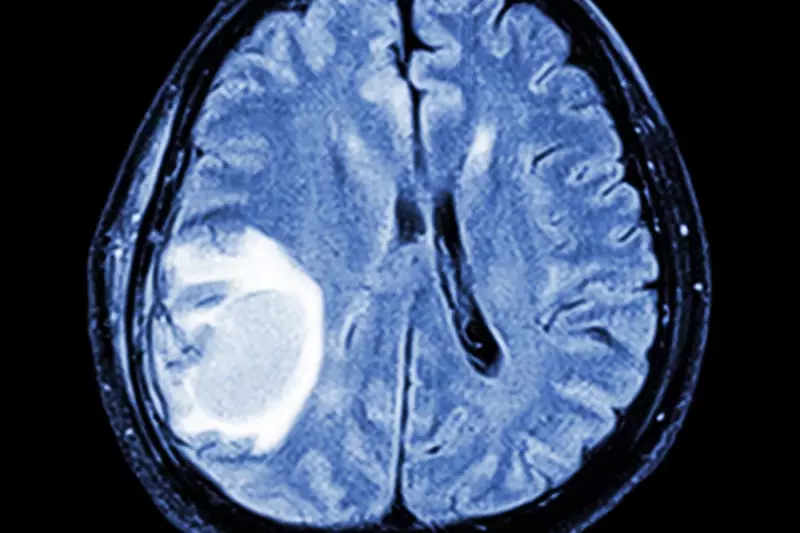

In a landmark scientific achievement that could revolutionise our understanding of neurological conditions, researchers have created the first comprehensive atlas of brain development. This pioneering work from the University of Oxford provides unprecedented insights into how the brain constructs itself, offering new hope for treating disorders like autism, ADHD, and schizophrenia.

Scientists have successfully mapped the intricate development of the mouse brain, creating what experts are calling a "blueprint" of cerebral construction. This detailed atlas tracks how different brain regions and cell types form and connect throughout development, revealing critical periods when things are most likely to go awry in neurodevelopmental conditions.